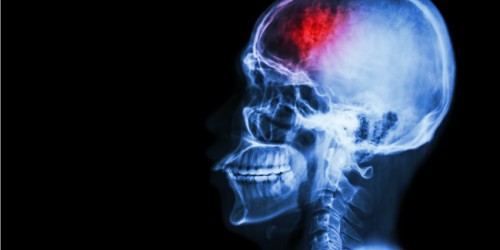

Good evening, folks. My friend has been administrated in hospital due to brain stroke. I know that he had previously had infective endocarditis. I would like to know if this could be the cause of stroke. I hope someone will be able to answer me. I would really appreciate all your replies.

Hello to you too. Infective endocarditis can be a cause for a brain stroke. Bacteria or fungi that cause endocarditis form a mass. This mass can be relocated. This is what we call emboli. This embolus can make an obstruction in a certain blood vessel and compromise blood supply of a certain organ. Brain can be one of them. In this way, there is a brain stroke. I hope I’ve helped with this. Bye!

Hello. I also agree with the previous post. My friend had infective endocarditis. However, he didn’t treat it properly. At the end he was hospitalized due to a brain stroke. That is why the treatment of infective endocarditis must be intensive and aggressive. One shouldn’t be playing with his/her health. I hope everything with your friend. Good luck with all! Bye!